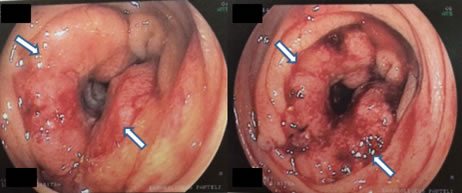

Η κολονοσκόπηση επιτρέπει την εκτίμηση της έκτασης του όγκου και τη διενέργεια βιοψίας για την επιβεβαίωση της διάγνωσης (Εικόνες 9, 10).

Εικόνα 10.

Αδενοκαρκίνωμα σιγμοειδούς σε κολονοσκόπηση

(Από το προσωπικό αρχείο του Γ. Θεοδωρόπουλου)

Σύγχρονοι καρκίνοι στο παχύ έντερο υπάρχουν σε ποσοστό 2-8%, ενώ πολύποδες συνυπάρχουν σε άλλα σημεία του παχέος εντέρου εκτός του κακοήθους νεοπλάσματος σε 20-30%.